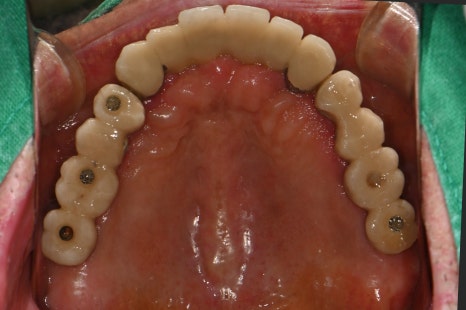

왼쪽 사진: 윗니는 대부분 임플란트 보철이지만 나사홀이 오픈되어 보완이 필요한 상태였습니다.

왼쪽 사진: 윗니 보철은 전체적으로 고정성이 좋고 교합이 안정적으로 설계되었습니다.